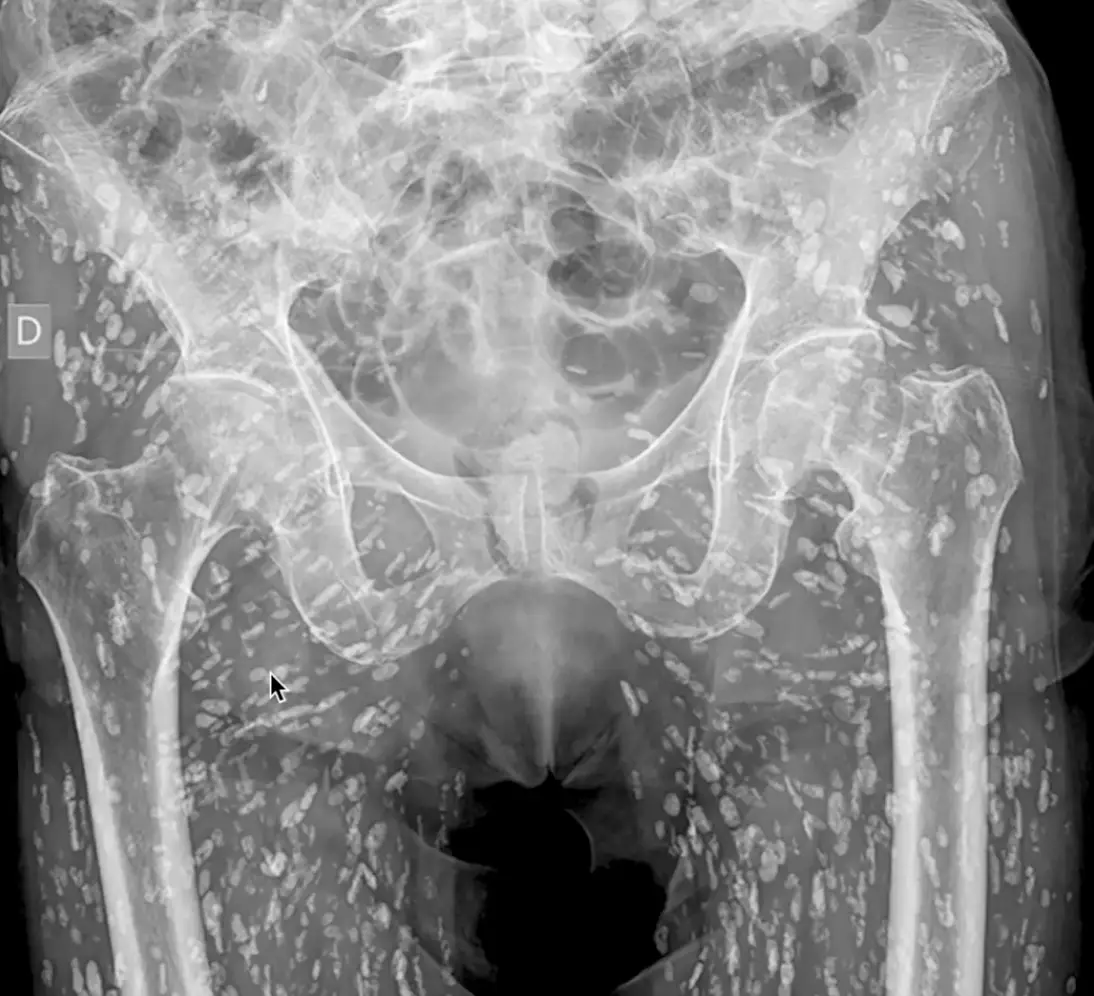

Doctor Sam Ghali shared an X-ray onto his social media account and explained what exactly people were looking at.

It is clearly a shot of a person’s pelvis, and the bones appear completely normal for the most part but one concerning detail is the appearance of white blotches scattered all over the person’s body.

In the video, he explained: “What is jumping right off the screen at us here is this film is riddled with these linear densities, and they are everywhere. So what the hell are they?

“This is a condition known as cysticercosis, essentially these are larval cyst of taenia solium, also known as the pork tapeworm.”

“These cysts can travel anywhere throughout the entire body, heavily to the muscular and soft tissue of the hips and the legs.”

The eggs then calcified in the body, which is why they look like white splotches.